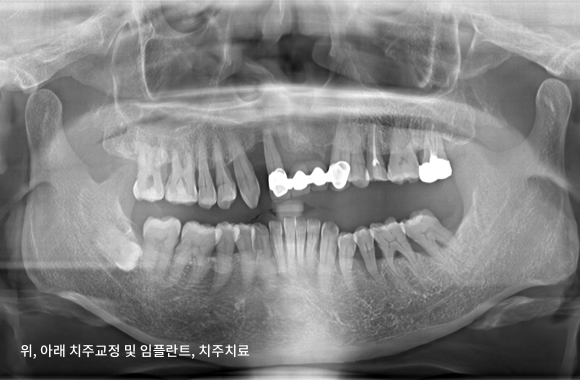

시니어 교정+임플란트